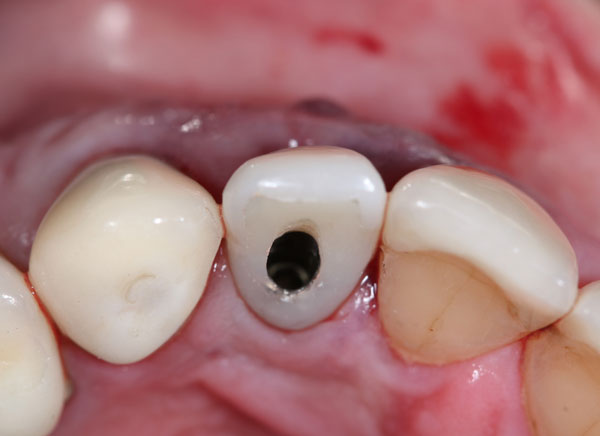

The Immediate Dentoalveolar Restoration (IDR) is a surgical and prosthetical technique established to broaden indications for immediate loading on individual teeth. In this way, tissue losses with varied extensions are reconstructed in the same surgical session of implant placement and provisional crown installation, reducing the number of interventions and keeping predictability on esthetic aspects. The IDR protocol was developed more than 12 years ago from the need to minimize the treatment time

Making the ideal temporary restoration

Construction of the emergency profile aiming the final restoration

g. Obtaining the ideal emergence profile of the crowns.

h. Modern concepts in implant-supported restorations.